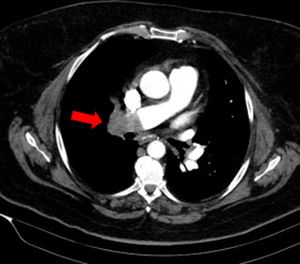

Mujer de 61 años, obesa, hipertensa y con enfermedad pulmonar obstructiva crónica (EPOC) que acudió al Servicio de Urgencias por disnea y dolor pleurítico en hemitórax derecho de 10 días de evolución. Presentaba importante trabajo respiratorio por lo que se inició ventilación mecánica no invasiva (VMNI). La radiografía de tórax fue anodina y el ecocardiograma mostraba un ventrículo derecho dilatado, pero normocontráctil. En la ecografía torácica se observaba una imagen hipoecogénica triangular de base periférica compatible con infarto pulmonar derecho (fig. 1). Se solicitó tomografía axial computarizada (TAC) torácico que evidenció defecto de repleción en arteria pulmonar principal derecha con extensión a ramas lobares, además de afectación alveolar pulmonar en lóbulo superior derecho, sugestivo de infarto pulmonar asociado (fig. 2). La ecografía aporta información extra muy valiosa y en ocasiones esencial para el manejo óptimo de los pacientes. El hallazgo más sugerente en la ecografía torácica de tromboembolismo pulmonar (TEP) es la presencia de lesiones hipoecoicas de forma triangular y base pleural rodeados por una línea pleural de aspecto normal con o sin derrame pleural asociado.